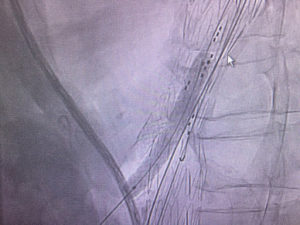

Gore Viabahn VBX balloon expandable covered stent might provide an excellent option for branched thoracoabdominal stent graft. Two VBX used today for successful bridging of coeliac axis and SMA branches. Easy delivery without sheath, great tractability, wide range of lengths and significant postdilatation bracket with no concerning shortening.